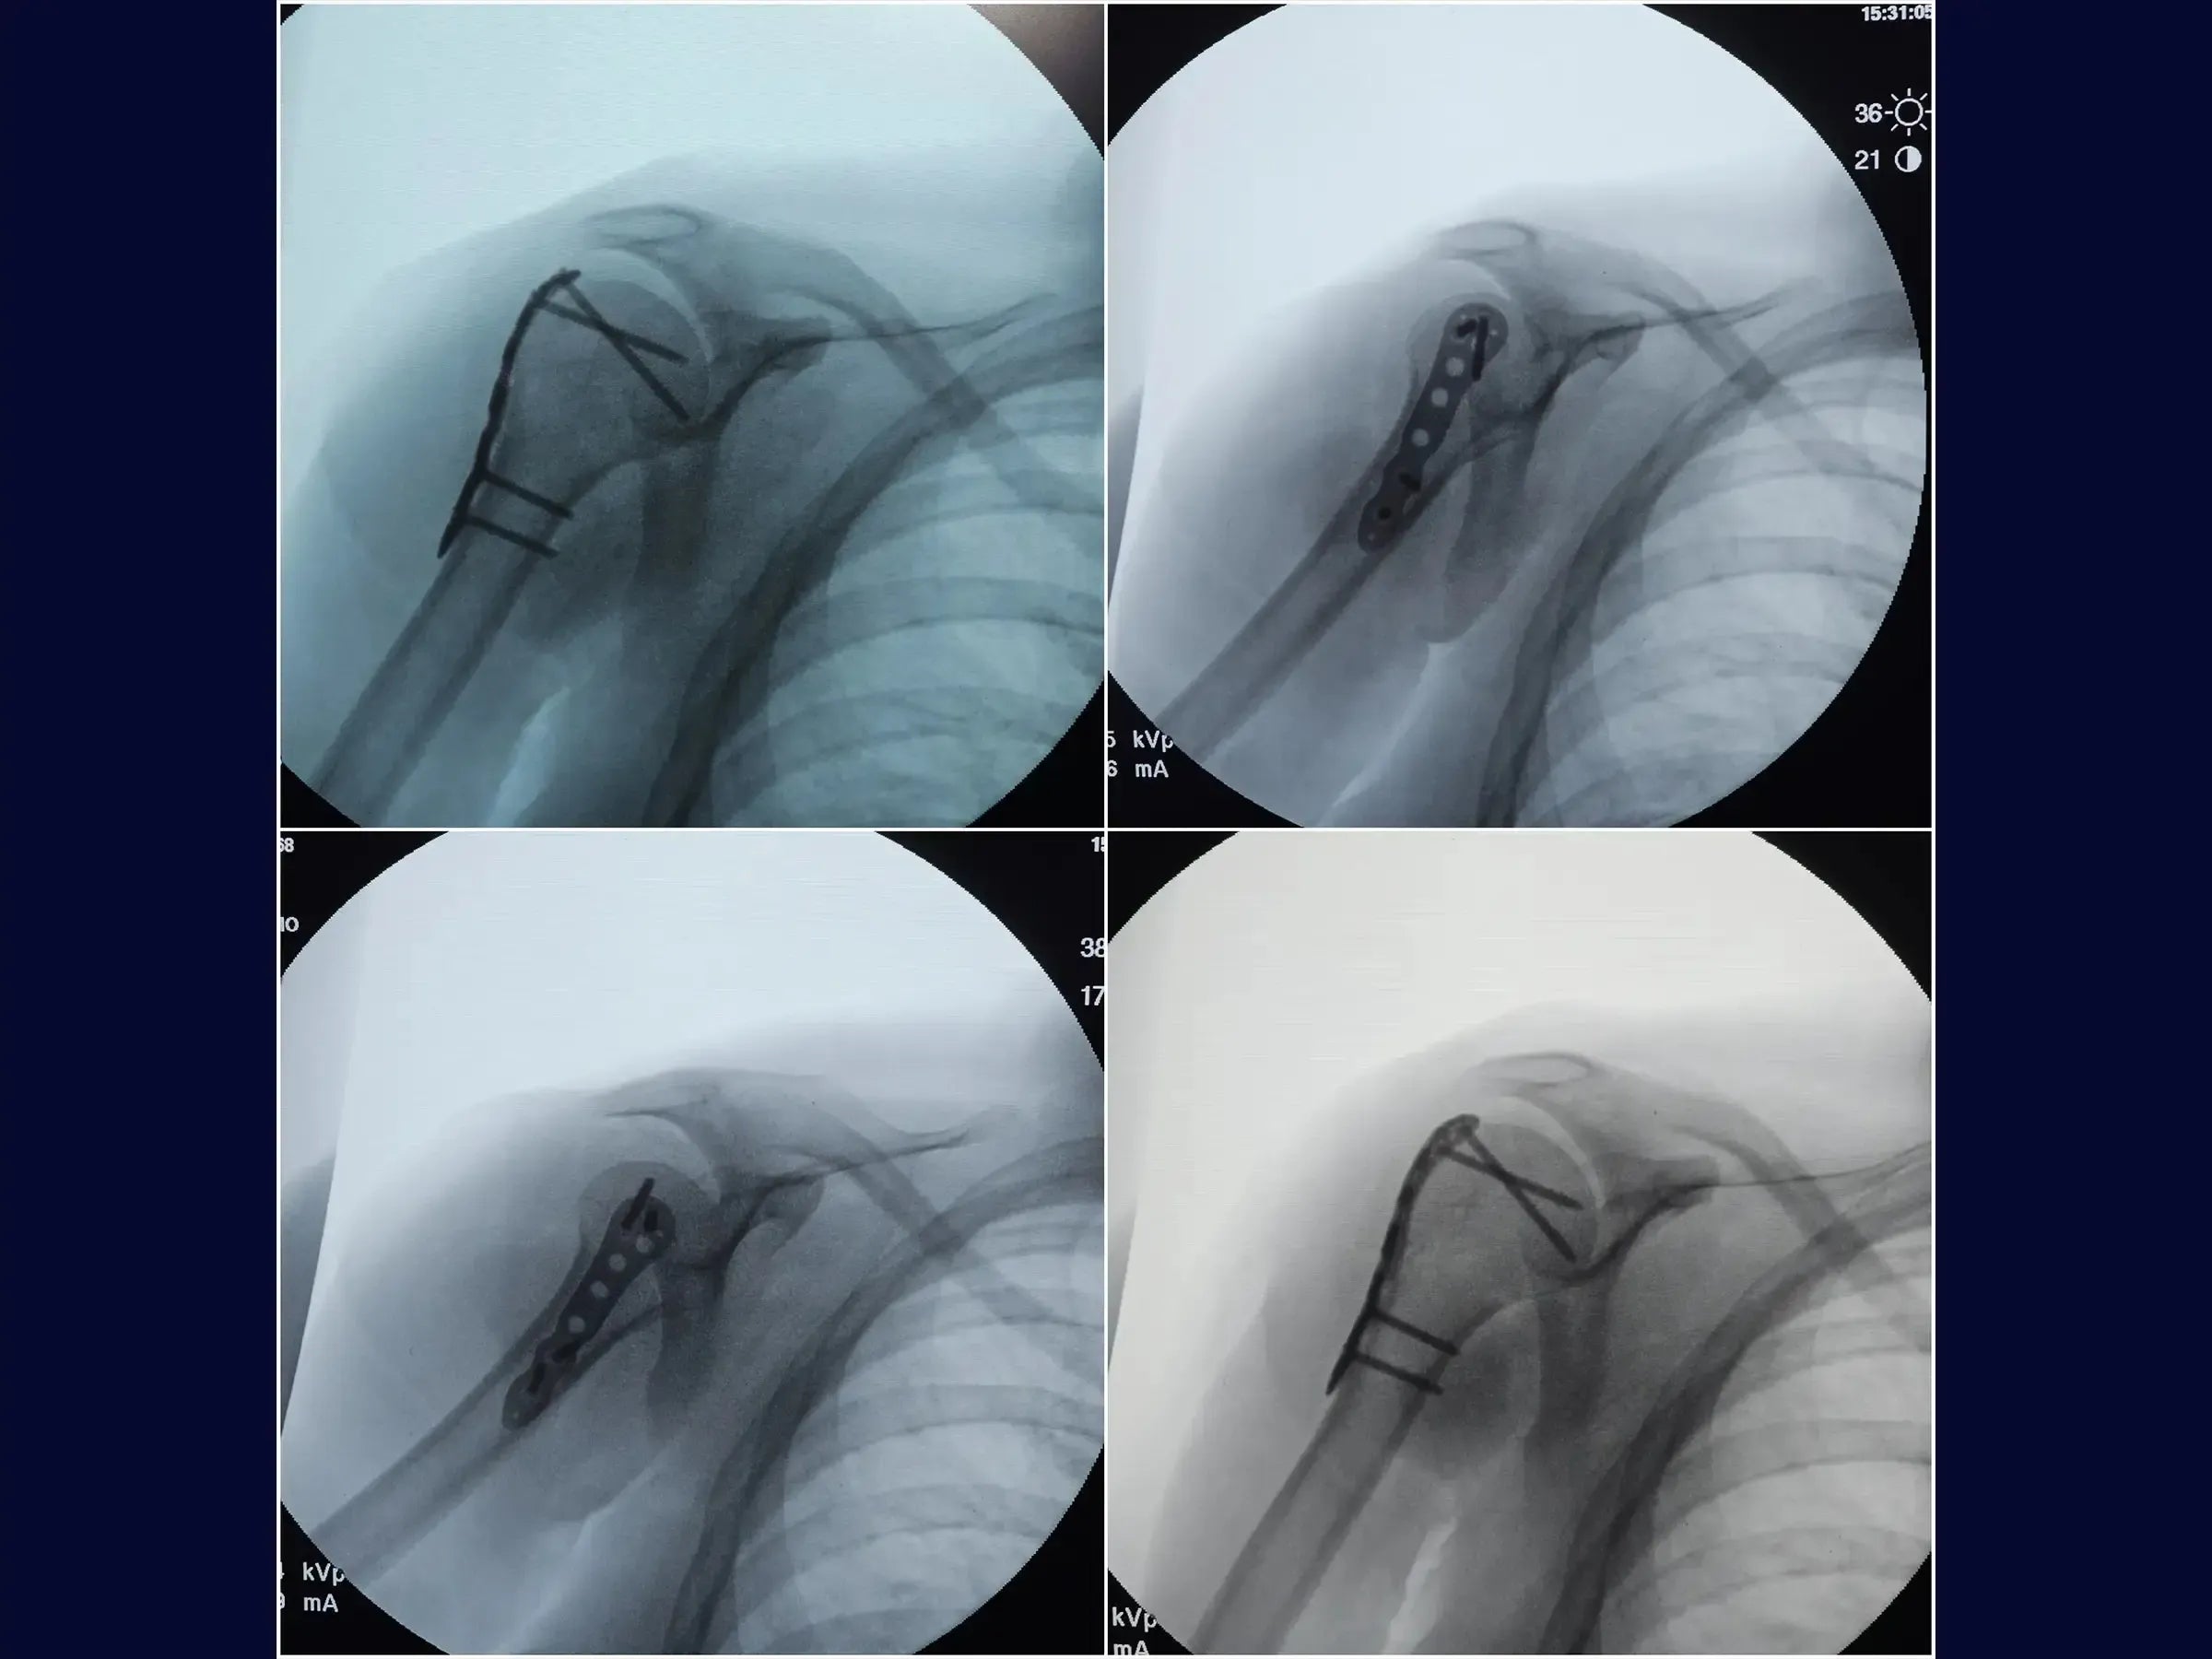

- Osteossíntese com placa bloqueada anatômica.

- Fixação Provisória e Definitiva Otimizadas: Sequência de fixação provisória com fio de Kirschner e aplicação de placa bloqueada anatômica, incluindo modelagem para evitar proeminências e técnicas de inserção de parafusos corticais e bloqueados.

- Resultados Clínicos Superiores: Demonstração de resultados cirúrgicos com preservação da anatomia, acesso limpo sem agressão muscular e sutura estética.